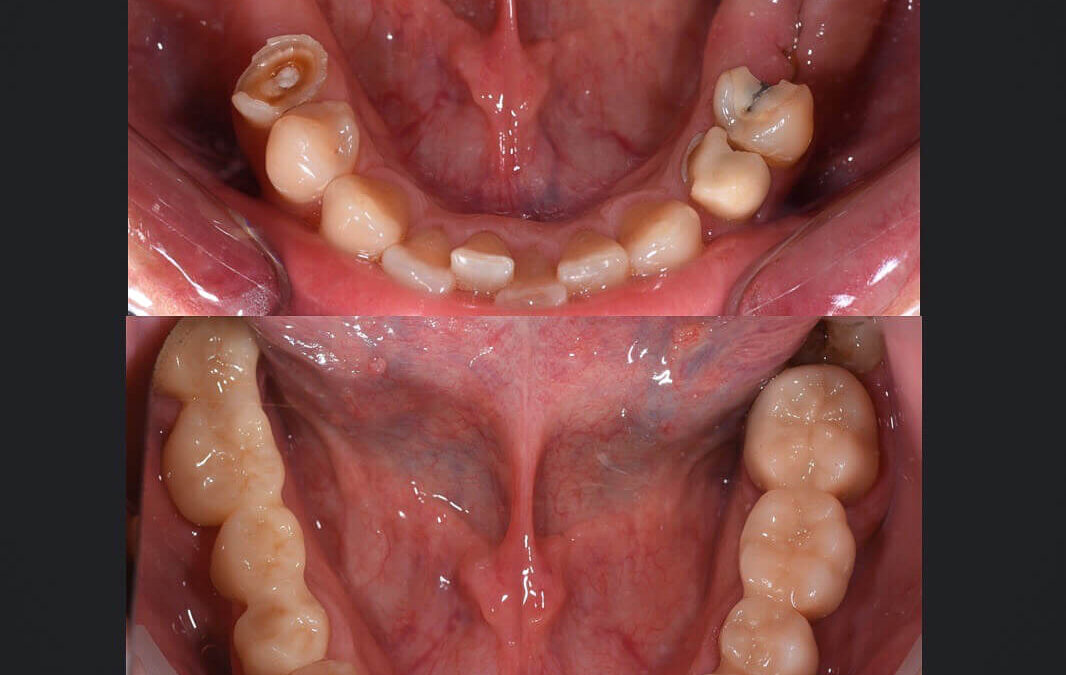

Előtte-utána: Hiányzó fogak pótlása

Kornél elvesztett fogainak pótlása miatt kereste fel fogorvosi rendelőnket, valamint szerette volna azt is, hogy metszőfogai esztétikusabbak legyenek. Alul és felül egyaránt több fogat áthidaló hiányt kellett orvosolni. Ehhez a rendelőnk több fogszakorvosa is...